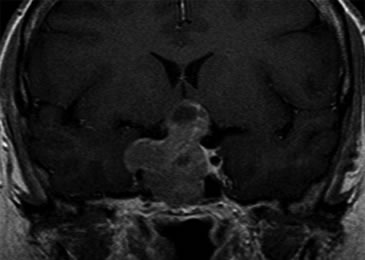

Se realizó una campimetría que evidenció una hemianopsia heterónima temporal. Una RM (Resonancia Magnética) posterior confirmó el hallazgo de adenoma hipofisario de 42 x 34 x 25 mm que realzaba moderadamente con en el contraste paramagnético, con varios quistes de retención glandular (el mayor de aproximadamente 1 cm de diámetro), con extensión supraselar e invasión del seno esfenoidal y seno cavernoso derecho con desplazamiento y compresión del quiasma óptico y del tallo hipofisario (Figuras 1 y 2).

Figura 1. Corte sagital en secuencia T1 con gadolinio.

Figura 2. Corte coronal en secuencia T1 con gadolinio.